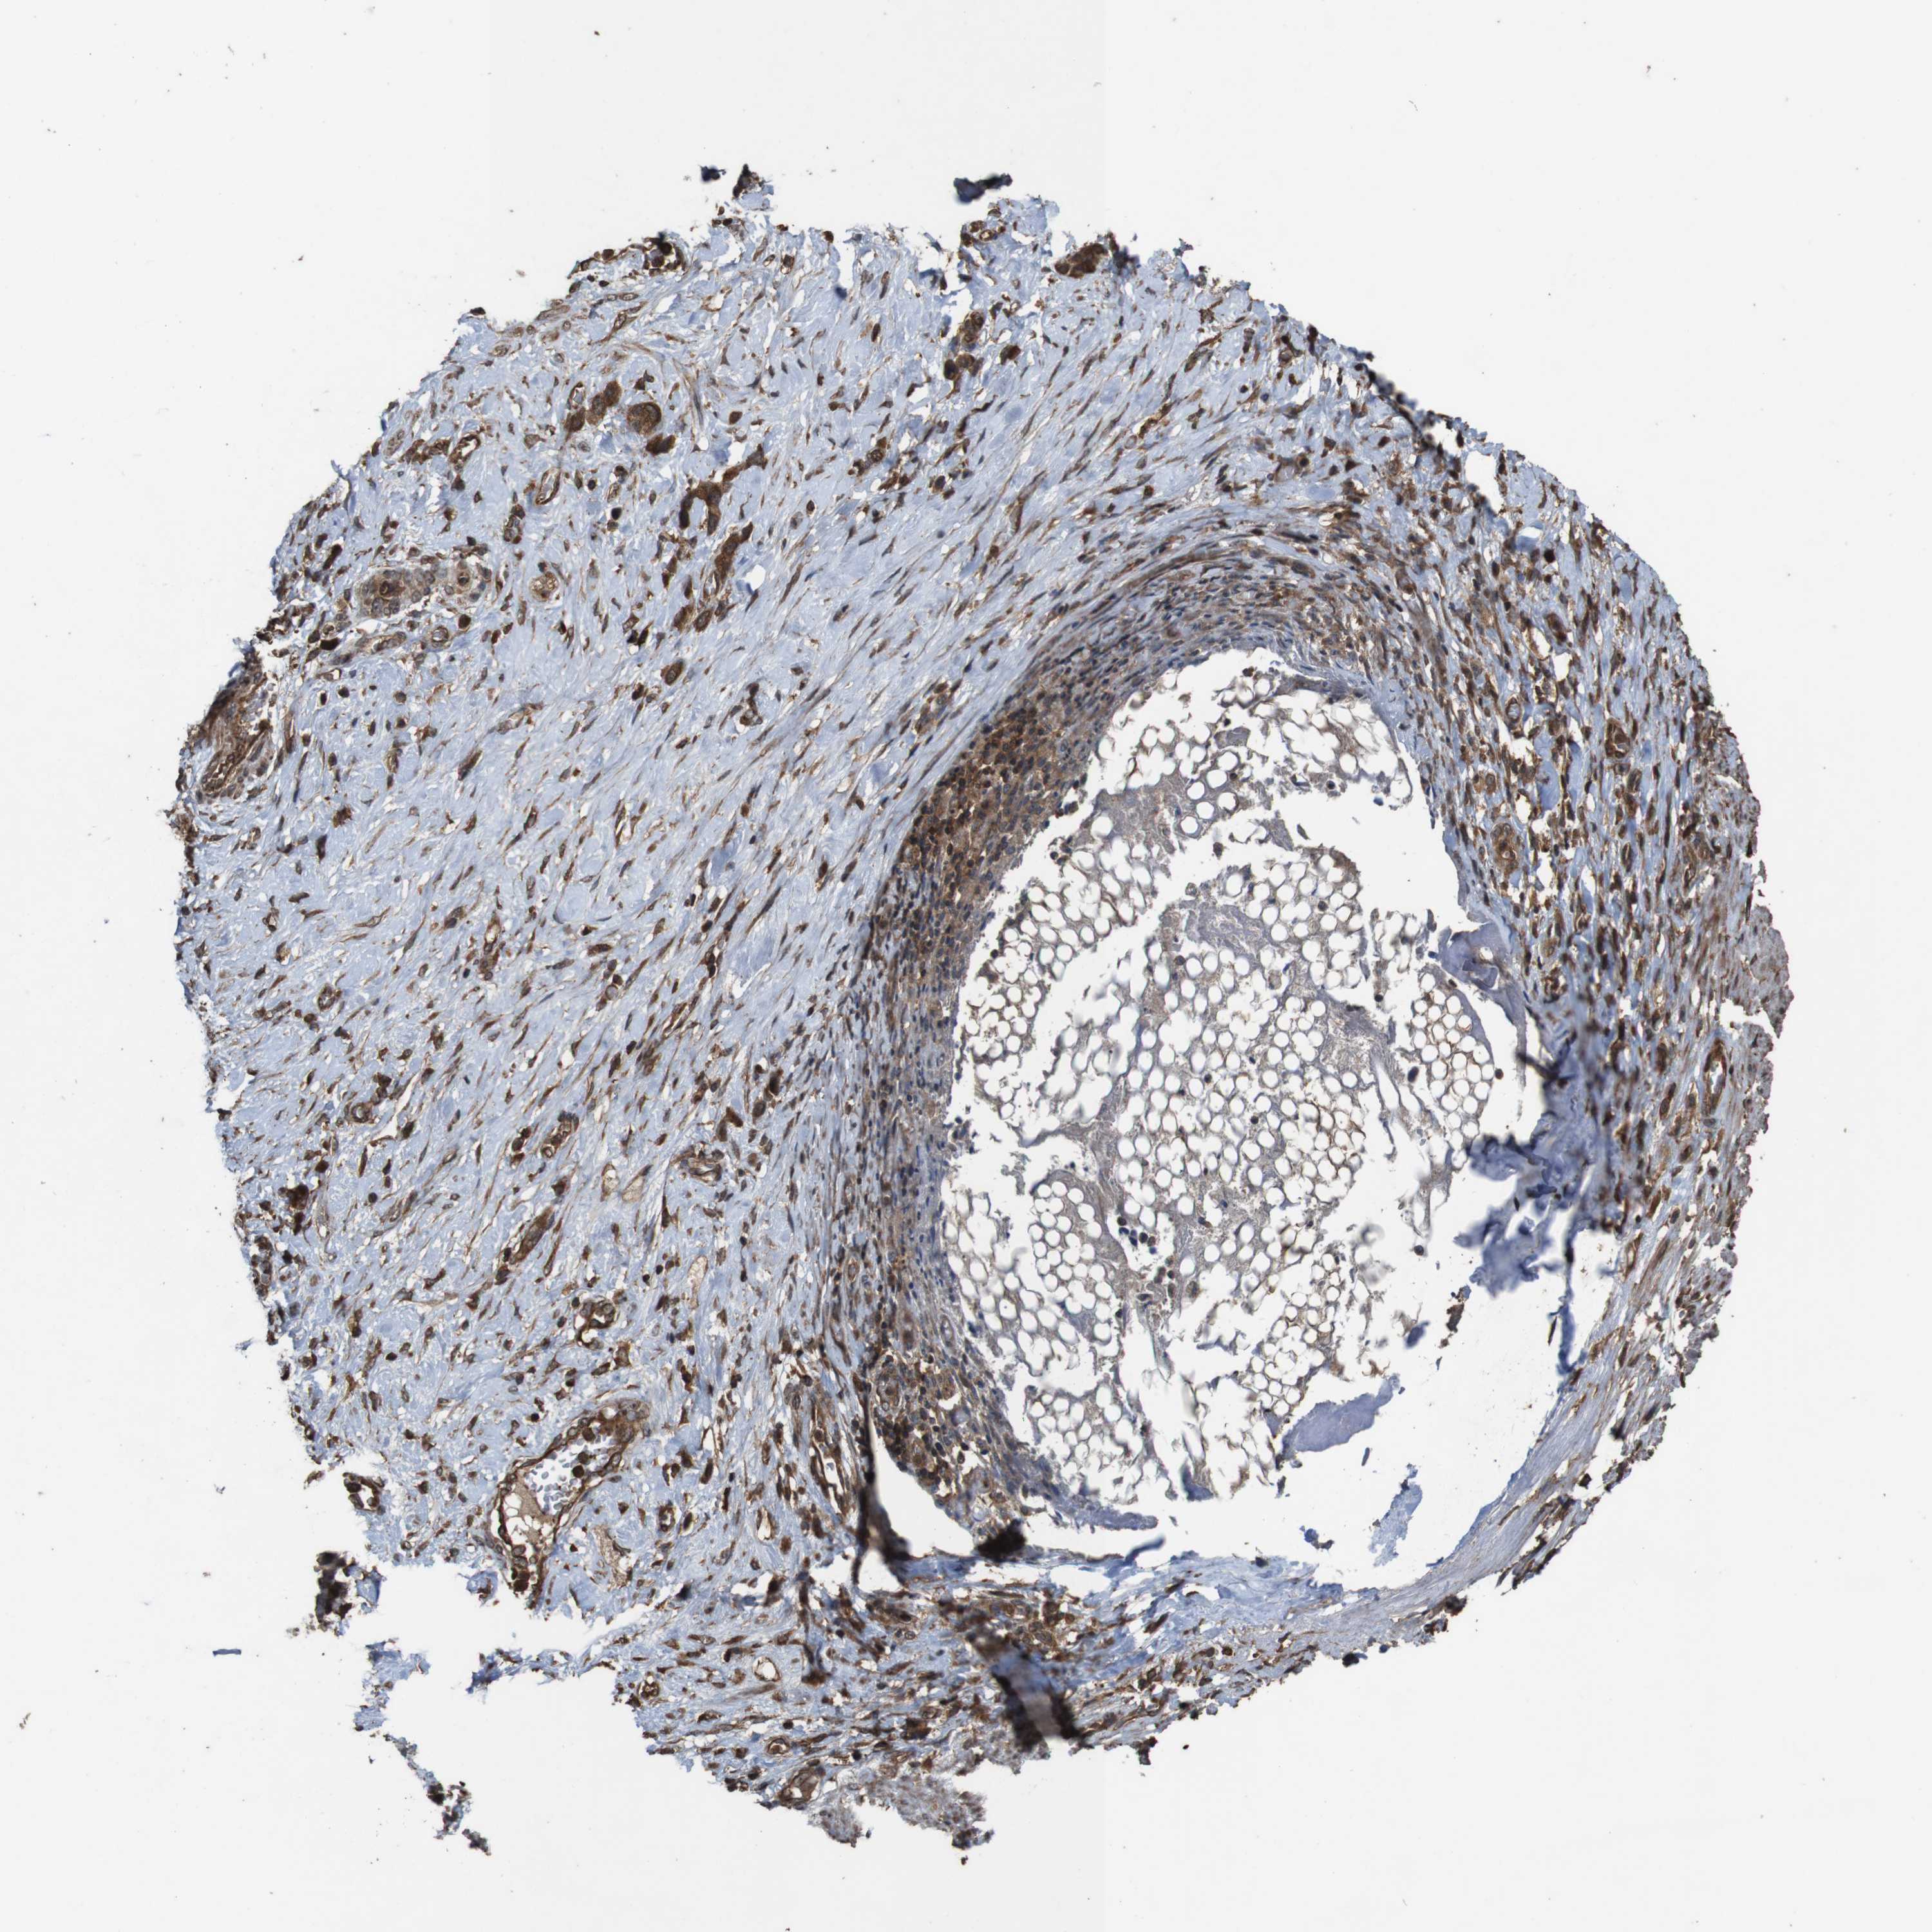

STOMACH CANCER - Protein expressioni

A mouse-over function shows sample information and annotation data. Click on an image to view it in a full screen mode. Samples can be filtered based on level of antibody staining by selecting one or several of the following categories: high, medium, low and not detected. The assay and annotation is described here.

Note that samples used for immunohistochemistry by the Human Protein Atlas do not correspond to samples in the TCGA dataset.

Antibody stainingi

Antibody staining in the annotated cell types in the current human tissue is reported as not detected, low, medium, or high, based on conventional immunohistochemistry profiling in selected tissues. This score is based on the combination of the staining intensity and fraction of stained cells.

Each image is clickable and will lead to virtual microscopy that enables deeper exploration of all samples and also displays staining intensity scores, fraction scores and subcellular localization as well as patient and tissue information for each sample.

Antibody HPA018951

Antibody CAB013716

Staining

High

Medium

Low

Not detected

Intensity

Strong

Moderate

Weak

Negative

Quantity

>75%

75%-25%

<25%

None

Location

Nuclear

Cytoplasmic/membranous

Cytoplasmic/membranous,nuclear

Adenocarcinoma, NOS

Adenocarcinoma, High grade